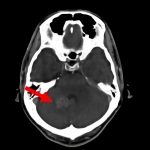

断層撮影

手術前2